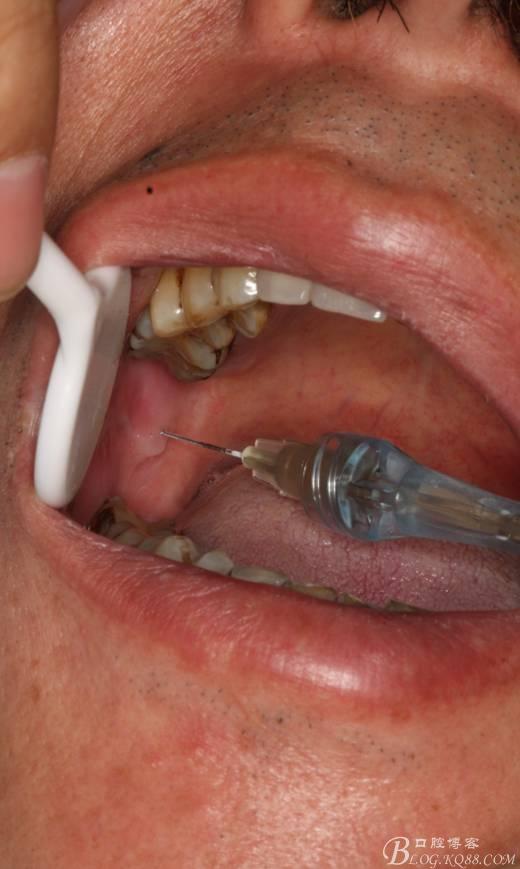

三、手術(shù)過(guò)程

1.麻醉